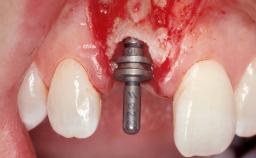

Late Flapless Placement of an Implant in a Maxillary Left Central Incisor Site

A 39-year-old male patient presented with a chief complaint of discomfort and gingival discoloration around his maxillary left central incisor. He was in good general health and was a non-smoker. His past dental history was significant because of the traumatic fracture of tooth 21 in a sporting accident at age 13. Initial dental treatment included endodontic therapy and a full-coverage restoration. The patient became symptomatic 5 years later, when structural failure of the tooth resulted in the dislodgment of the crown. Endodontic retreatment, apical surgery, and post-and-core restoration were performed.

| Placement Protocol | Early or late implant placement |

| Bone Volume | Deficient horizontally, requiring prior grafting |